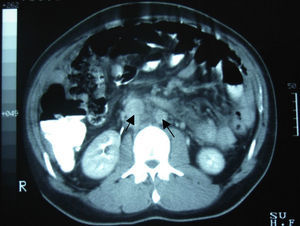

Clinical caseA 24-year-old male patient, with no history of surgeries, trauma, autoimmune diseases or medication intake. He presented symptoms 4 weeks before his admission, including sudden colic, sporadic, 10-minute long abdominal pain in the right hypochondrium, accompanied by early satiety, hyporexia and involuntary loss of 10kg of weight in the last 3 months. The patient denied having fever, asthenia, adynamia, as well as other relevant history. On admission, he was found to be haemodynamically stable, without fever and without relevant pathological data. He presented a soft, depressible, globus abdomen, with diminished peristalsis, without pain on palpation and without visceromegaly. Alpha-fetoprotein of 4.28IU/ml, CA-125 of 110IU/ml and lactic dehydrogenase of 1025IU/l were observed. The abdominal computed tomography showed the presence of multiple nodular-to-ovoid lesions in the abdominopelvic cavity, of increased density, which had no apparent organic origin, the largest of which was 6cm×4cm, and were well defined. These findings suggested peritoneal carcinomatosis with metastatic retroperitoneal adenopathies (Figs. 1 and 2).

Among the studies conducted for its diagnosis, the abdominopelvic computed tomography generally involves one or multiple tumours of lobulated and well-defined borders, with hyperdense and heterogeneous soft tissue, with hypodensity areas related to necrosis and haemorrhage foci, located in the intraperitoneal region, without apparent abdominal organic origin. About 50% may present adenomegalies and 20% may present calcifications. Bellah et al.15 reported that lesions were located in the vesical rectum and/or urinary rectum in 82% of the cases.3–5,15